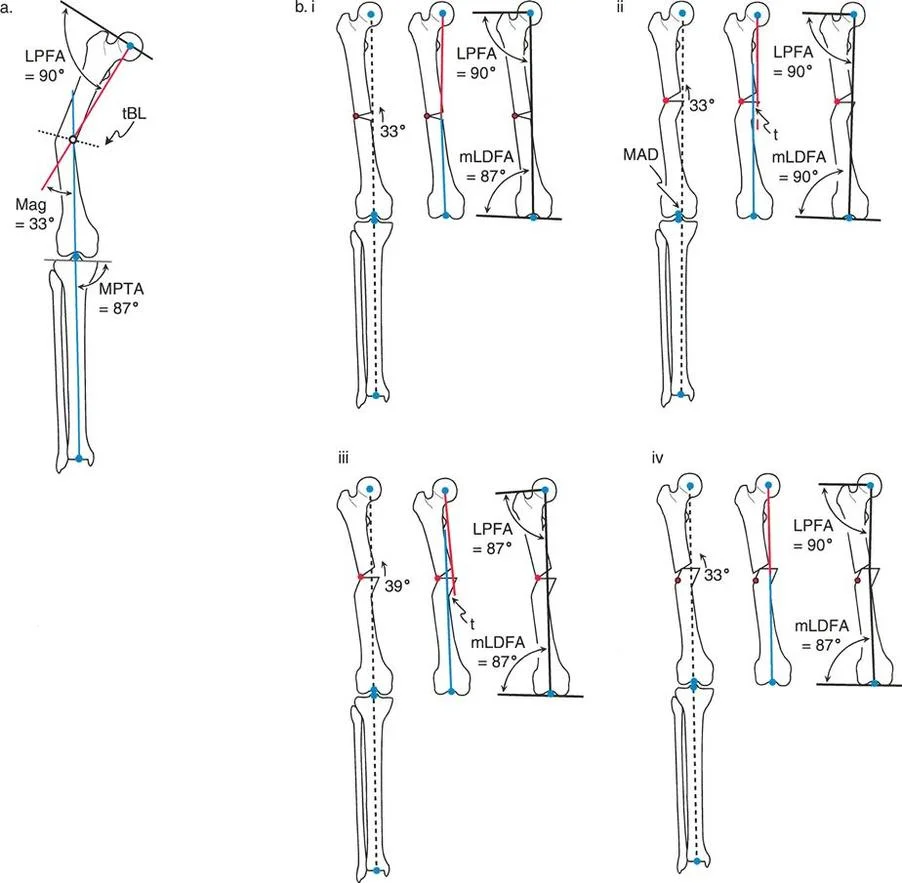

- mLDFA (mechanical Lateral Distal Femoral Angle) This is the lateral angle formed between the mechanical axis of the femur and the distal femoral joint line. The normal value is 87 degrees, with a standard range of 85 to 90 degrees. An mLDFA greater than 90 degrees indicates a distal femoral varus deformity. An mLDFA less than 85 degrees indicates a distal femoral valgus deformity.

- LPFA (Lateral Proximal Femoral Angle) This is the lateral angle formed between the mechanical axis of the femur and a line drawn from the tip of the greater trochanter to the center of the femoral head. The normal value is 90 degrees (range 85 to 95 degrees).

- MPTA (Mechanical Proximal Tibial Angle) This is the medial angle formed between the mechanical axis of the tibia and the proximal tibial joint line. The normal value is 87 degrees (range 85 to 90 degrees). An MPTA less than 85 degrees indicates proximal tibial varus. An MPTA greater than 90 degrees indicates proximal tibial valgus.

The Center of Rotation of Angulation (CORA) represents the apex of the deformity. To find the CORA, the surgeon draws the Proximal Mechanical Axis (PMA) line and the Distal Mechanical Axis (DMA) line.

* The PMA is drawn by taking the normal joint orientation angle from the proximal joint and extending a line down the shaft.

* The DMA is drawn by taking the normal joint orientation angle from the distal joint and extending a line up the shaft.

* The exact point where the PMA and DMA intersect is the CORA.

Osteotomy Rule One Pure Angulation

When the osteotomy line and the ACA both pass directly through the CORA, pure angular correction is achieved.

The Biomechanical Result

Osteotomy Rule Two Angulation with Translation

When the ACA passes through the CORA, but the osteotomy line is made at a different level (either proximal or distal to the CORA).

The Biomechanical Result

The mechanical axis and joint orientation angles are perfectly restored. However, because the bone cut is made at a distance from the hinge point, the bone segments will mathematically translate relative to one another. This creates a visible "bump" or step-off in the anatomic axis. While the bone looks jagged on an x-ray, the load-bearing mechanical axis is flawless.

Osteotomy Rule Three Secondary Deformity

When the osteotomy line and the ACA are both placed at a level different from the CORA.

The Biomechanical Result

A secondary translational deformity is created. While the angular deformity may appear to be corrected, the mechanical axis will not be fully restored. The proximal and distal mechanical axes will be parallel but not collinear, resulting in residual Mechanical Axis Deviation (MAD).

The Opening Wedge Osteotomy Sequence

- Biomechanics and Limb Length The opening wedge inherently lengthens the limb. The ACA is placed on the convex side of the deformity (the side that acts as the hinge).

The Closing Wedge Osteotomy Sequence

- Biomechanics and Limb Length The closing wedge inherently shortens the limb. The ACA is placed on the concave side of the deformity.